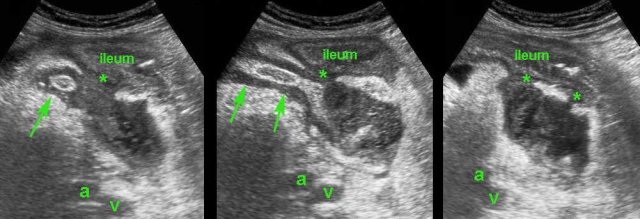

This 75-year old lady had subsiding symptoms after 7 days of RLQ pain, and she told us that she was feeling much better now.

US showed an inflamed appendix (arrow) with an adjacent abscess, walled-off by inflamed fat and the terminal ileum.

There were echolucent connections (*) between the abscess and the ileum, indicating spontaneous evacuation (a and v = right iliac artery and vein).

CT scan confirmed the anatomic situation.

The patient was completely cured with only antibiotics.

Three years later she underwent CT for sigmoid diverticulitis which allowed us to take a look at her appendix region.

The appendix (arrows) was small and still had intimate contact with the ileum (il.)

Another 4 years later, at age 82, she is still doing fine.